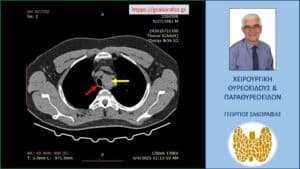

Αξονική τομογραφία – απεικόνιση σε κατά μέτωπο διατομή. Εμφανής η μεγάλου βαθμού διόγκωση και η κατάδυση σε βάθος του αριστερού λοβού (κίτρινο βέλος), που φθάνει στις παρυφές του αορτικού τόξου (πράσινο βέλος), με την τραχεία (κόκκινο βέλος) να απωθείται προς τα δεξιά από τον διογκωμένο αριστερό λοβό.

Καταδυόμενη βρογχοκήλη με κατάδυση σε βάθος στο θώρακα – εικόνα στην αξονική τομογραφία (κατά μέτωπο διατομή, σε άλλο επίπεδο). Εμφανής η μεγάλου βαθμού διόγκωση και η κατάδυση σε βάθος του αριστερού λοβού (κίτρινο βέλος), που φθάνει στις παρυφές του αορτικού τόξου (πράσινο βέλος), με την τραχεία (κόκκινο βέλος) να απωθείται προς τα δεξιά από τον διογκωμένο αριστερό λοβό. Ο καταδυόμενος αριστερός λοβός φθάνει σε βάθος λίγο πιο πάνω από τον διχασμό της τραχείας στους δύο στελεχιαίους βρόγχους.